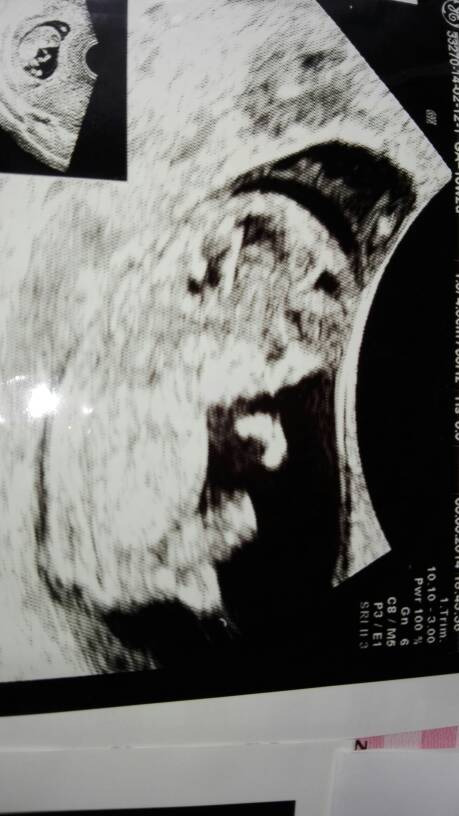

Jakiś chyba lekki postrzal mnie dopadł. A tego 6.04 to po L4 idę ale może znowu coś tam podgladniemy